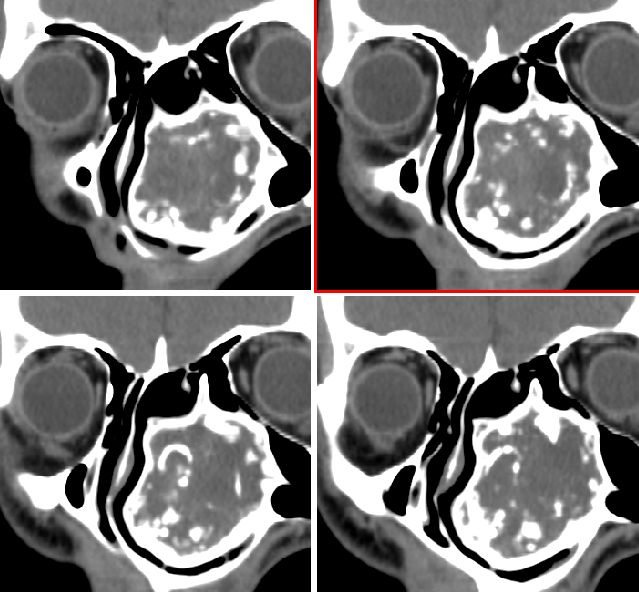

男性,20岁,面部包块8年余,进行性增大

我们考虑来源于上颌骨的骨化性纤维瘤,请大家指教

左侧鼻腔内囊性膨胀性骨质破坏,内示多发点环状钙化,周边骨质硬化.局部与上颌相连部骨质呈毛玻璃样改变.

左侧鼻腔内囊性膨胀性骨质破坏,内示多发点环状钙化,周边骨质硬化.

病变较大,密度不均,内见钙化及脂肪密度影,边缘锐利,相邻窦腔清晰,病史较长,考虑良性病变间叶性错构瘤可能。